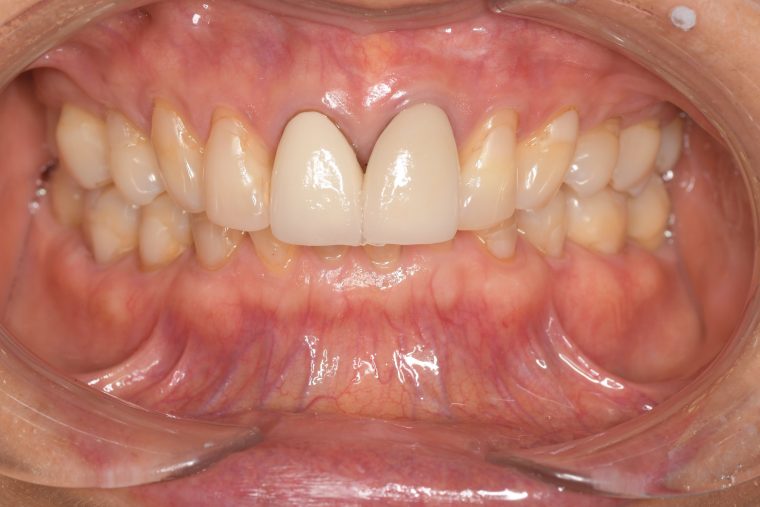

Before

症例

After

年齢・性別 75歳・女性

主訴 主訴:左上奥の歯ぐきが腫れた

治療部位:左上下奥歯、右下奥歯

特記事項 ・65年前に矯正治療をしてから歯をずっと大切にしてきたので、なるべく抜歯はしたくない。

・上の前歯は10年前にお孫さんがぶつかってきて、神経の治療をした。

・食いしばりをする癖がある為ナイトガード(夜間につける歯を保護するマウスピース)を作製し使用して頂いている。

担当者所見 左上は歯ぐきがかなり腫れていたが、歯石除去とホームケア(歯ブラシ、歯間ブラシSサイズ、ミクリンタフトブラシ)と抗生物質(軟膏)により腫れが落ち着いた。

それに加え、過度な力がかからないよう、ナイトガードを毎日使って頂くことと、日中の食いしばりにも気をつけてもらうようにした。

これは上の前歯を守るためのものでもあるので、必ず使用して頂いています。(上の前歯は神経がない為栄養が行き届かないので神経がある歯に比べ脆く根っこにヒビが入りやすい)

そして現在は定期検診で毎回異常がないか確認し、ホームケアではなかなか届かない歯周ポケット内のクリーニングを行っています。一度骨が溶けてしまっている為、歯周ポケットは残りますが、その後再発することは今のところなく、定期検診で今後もしっかり管理していきます。